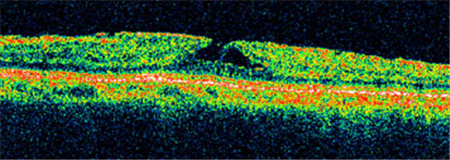

Ⅰ期黃斑裂孔通常無需手術(shù),若裂孔惡化至Ⅱ-Ⅳ期就需要考慮進(jìn)行手術(shù)治療。北京希瑪林順潮眼科醫(yī)院通過學(xué)相干斷層掃描來診斷黃斑裂孔,可清楚照出玻璃體及視網(wǎng)膜的情況,了解患者黃斑裂孔的大小、位置等。